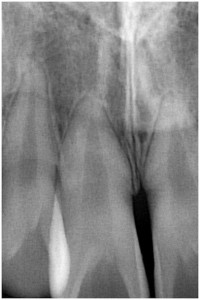

2013年10月19日 短根 ブログ 新着情報 前歯の根が短いです。 このような場合の歯列矯正には慎重を要します。 前歯を強打したり、出っ歯の影響だったり短くなる原因も様々。 とにかく長持ちするように心がけています。